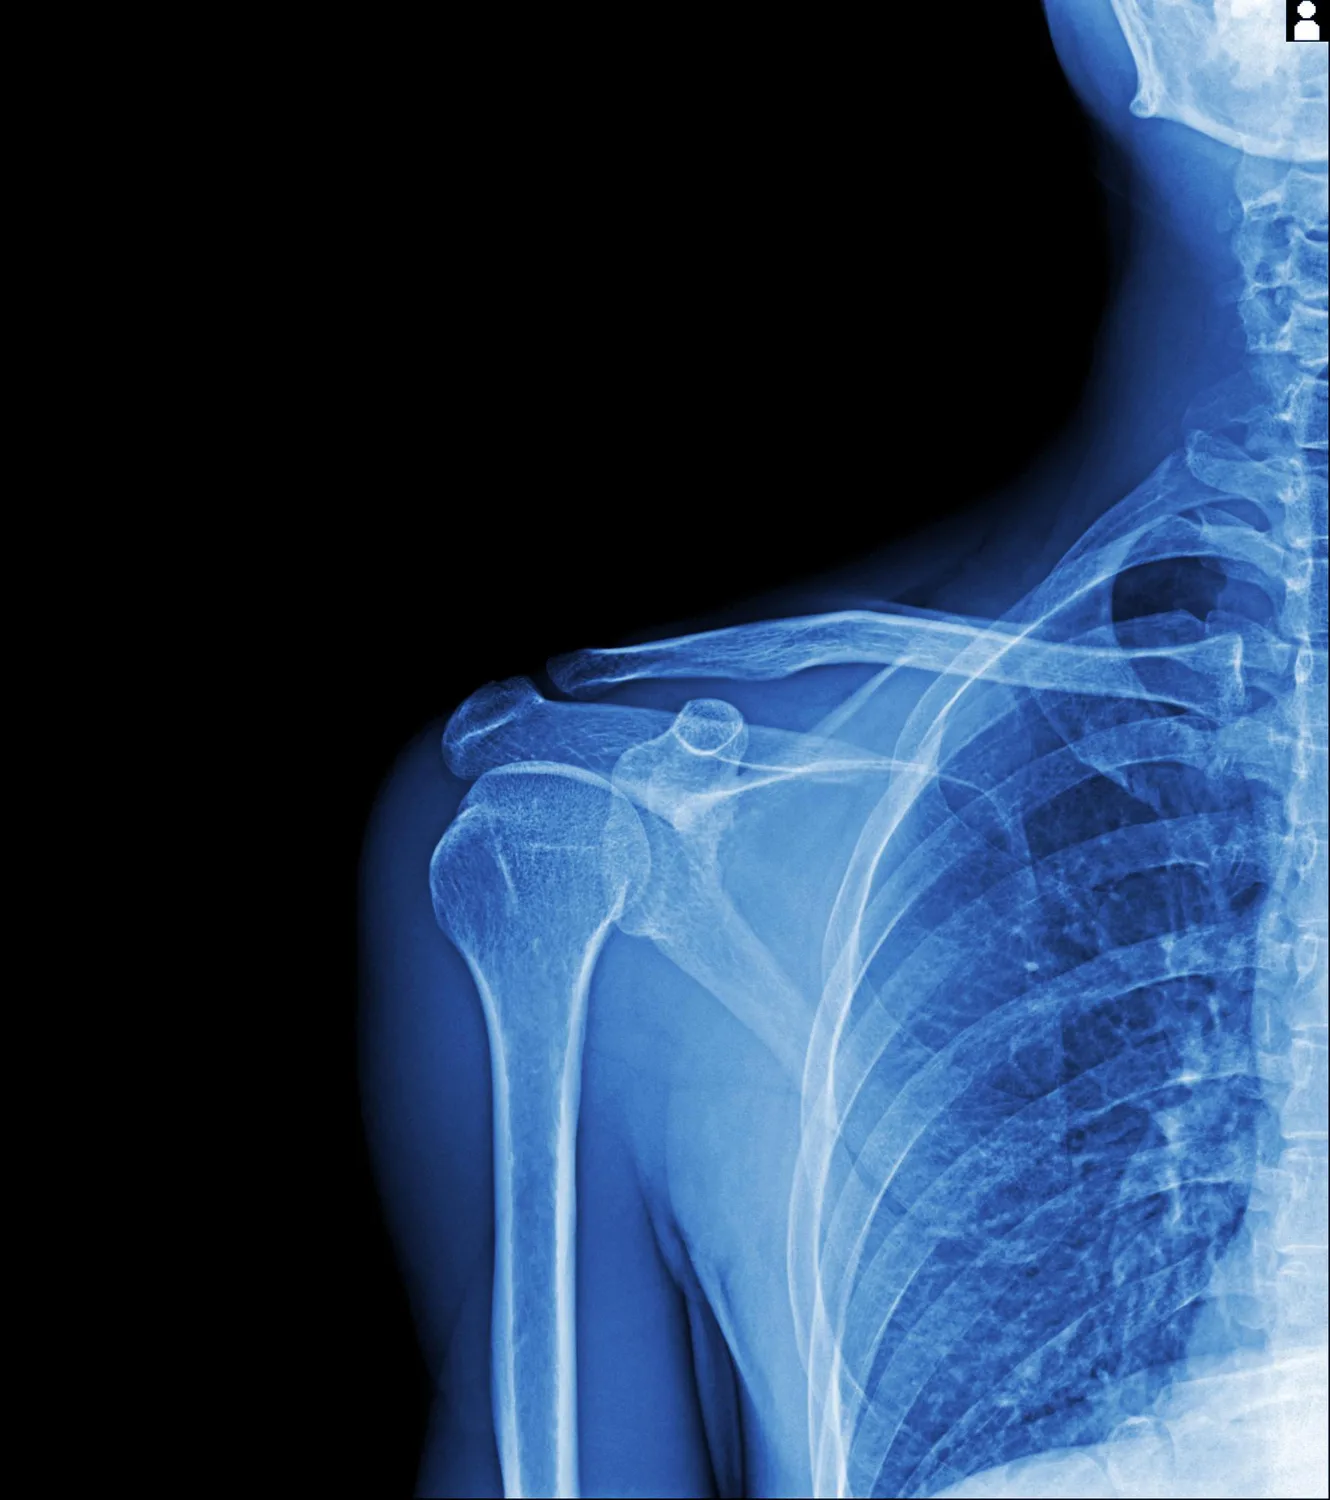

تا امروز نتایج مطالعات نشان داده بودند که این ذرات میتوانند وارد بخشهای مختلف بدن مثل مغز، جُفت، کبد، کلیه و اندامهای تولیدمثلی شوند. حالا پژوهشهای تازه میگویند میکروپلاستیکها خود را به اعماق استخوان هم میرسانند و ممکن است سلامت آن را هم تحتتأثیر قرار دهند.

برخی تحقیقاتی که روی انسان انجام شده، نشان دادهاند این ذرات پس از عبور از روده وارد جریان خون میشوند، به استخوان میرسند و آنجا تجمع پیدا میکنند. علاوه بر این، مطالعات حیوانی گزارش کردهاند که چنین مواجههای میتواند رشد استخوان را کاهش دهد.